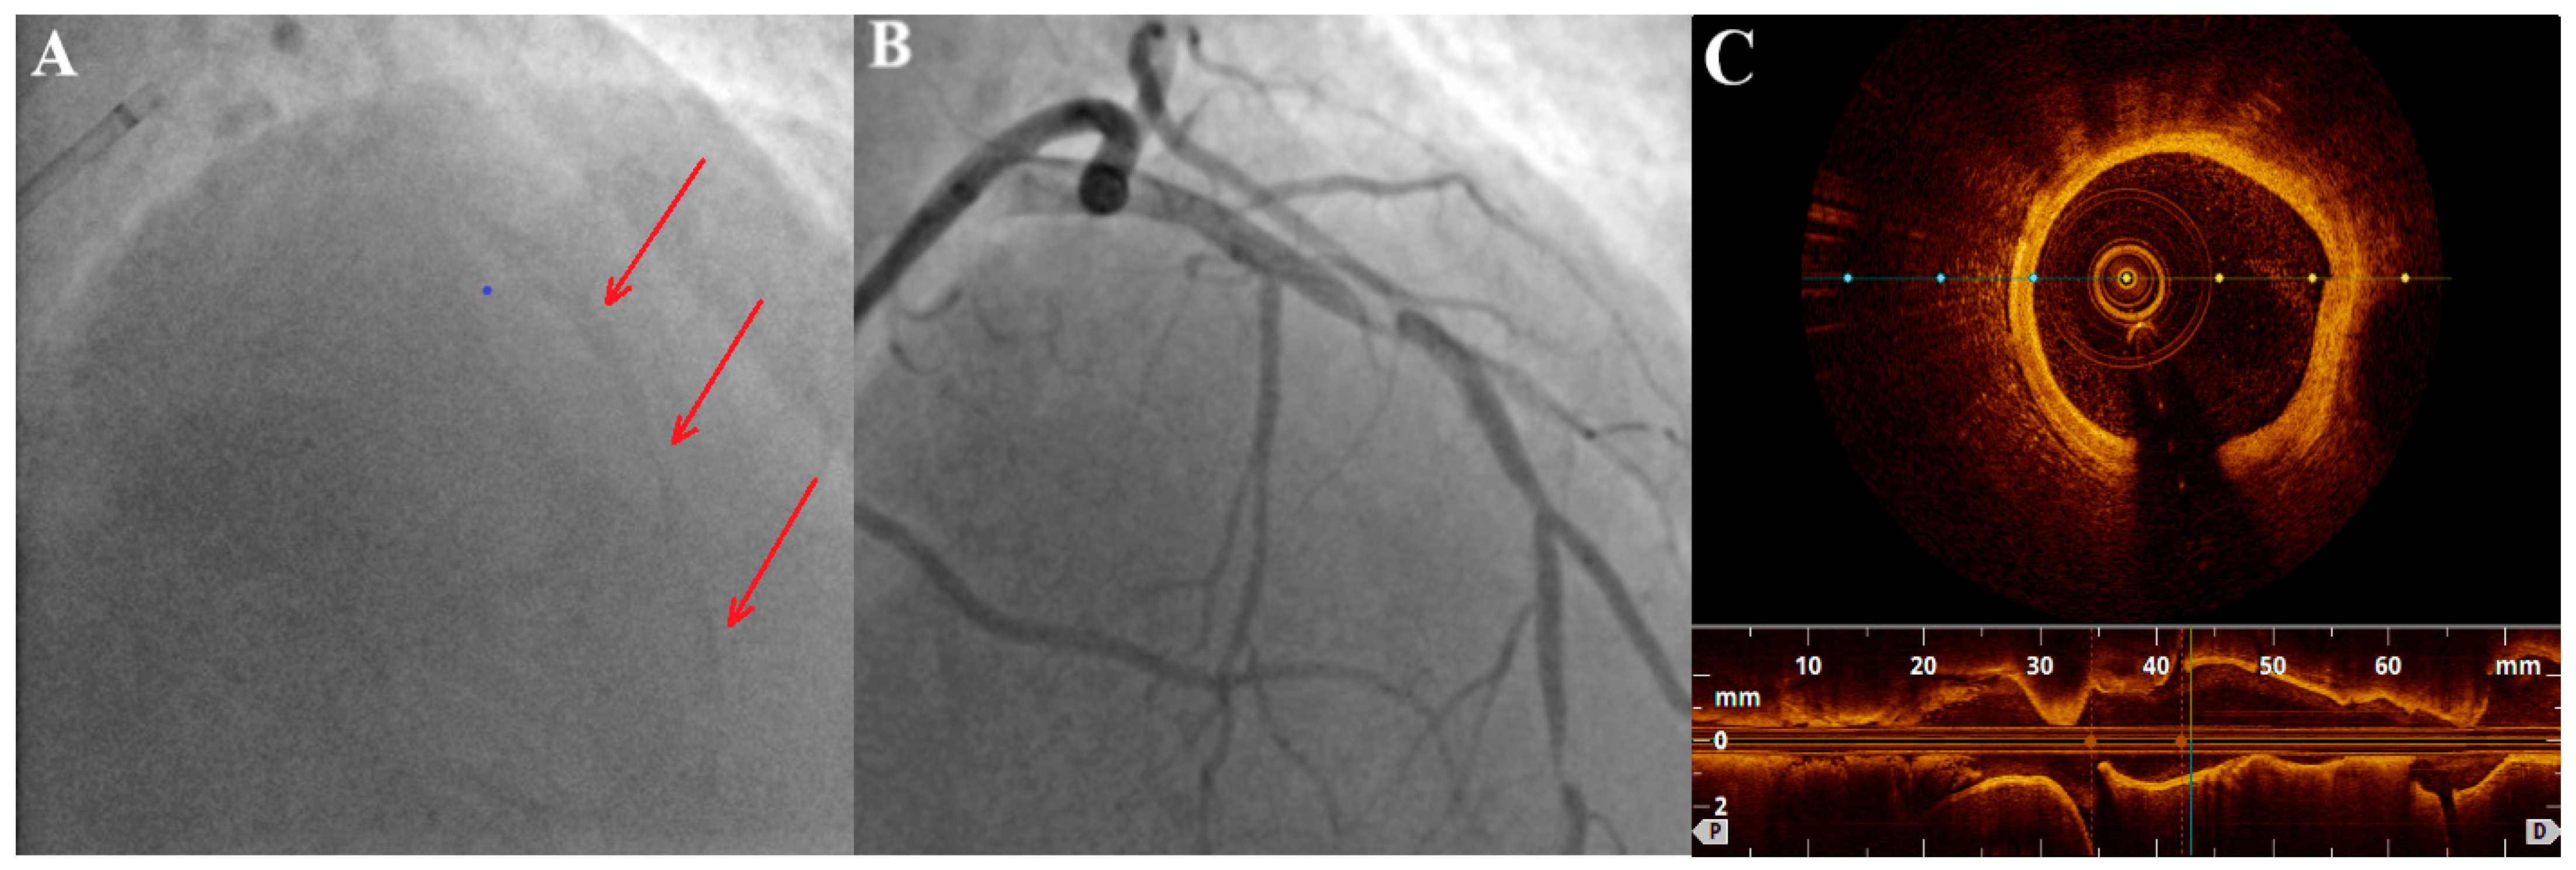

2.3. Intravascular Imaging: IVUS (Intravascular Ultrasound) and OCT (Optical Coherence Tomography)